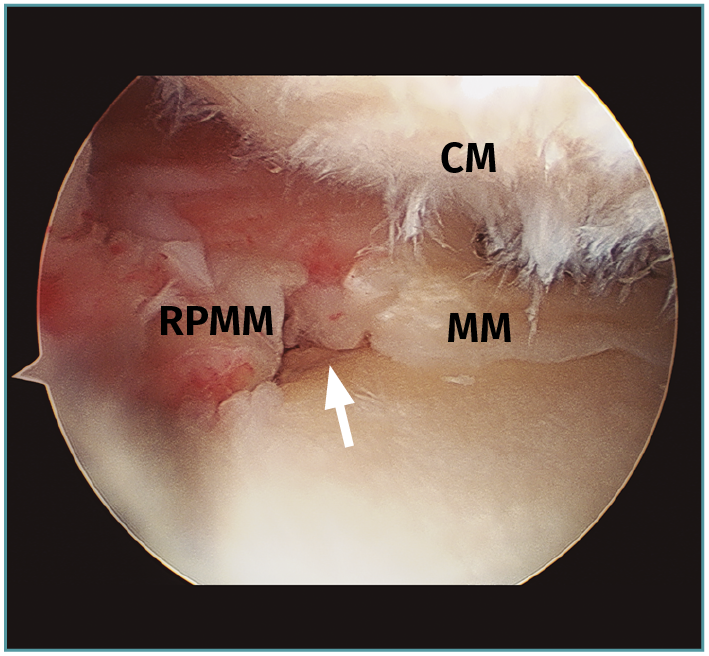

Se considera lesión de la raíz a la avulsión de la misma del hueso con o sin fragmento óseo (Figura 1), o bien a la rotura (normalmente radial) de la región adyacente al mismo (< 1 cm) (Figura 2)(3). Esta puede ser de naturaleza degenerativa o traumática (generalmente asociada a lesiones ligamentosas de la rodilla).

Figura 2. Rotura radial de la raíz posterior del menisco medial (MM). CM: cóndilo medial con condropatías; RPMM: raíz posterior del MM. Flecha: zona de rotura radial.